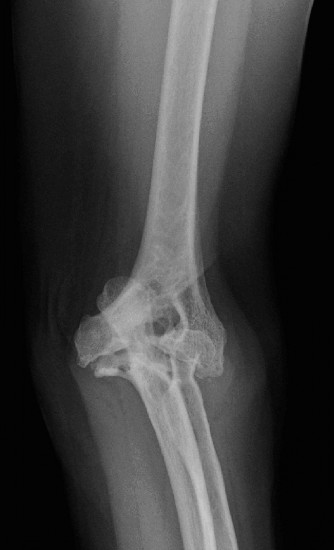

Treat a patient with infected total shoulder arthroplasty? CASE 21 A 70-year-old, right-hand-dominant female presents to clinic complaining of 4 years of gradually worsening chronic right shoulder pain and stiffness. She says the pain is worse at night and with any range of motion, denies a history of trauma, pain in other extremities, or numbness or tingling of the right upper extremity. She notes that her mother suffered from rheumatoid arthritis that affected her shoulder. Physical examination reveals decreased muscle bulk over the right supra- and infraspinatus fossae compared to the contralateral side, limited active and passive ROM, marked weakness with external rotation, and 4+/5 strength with shoulder abduction. X-rays of the right shoulder are shown in Figures 2–58 and 2–59.

Figure 2–58

Figure 2–59

The correct answer is (C). Rotator cuff tear arthropathy consists of a combination of rotator cuff insufficiency, glenohumeral joint degenerative changes, and superior humeral head migration. It is more common in women and also more often found on the dominant side. The patient’s clinical examination with weakened external

rotation and muscle atrophy signaling incompetent supra- and infraspinatus muscles point to rotator cuff insufficiency, and her plain films reveal narrowed glenohumeral joint space as well as superior migration of the humeral head. Choice D is incorrect because, while radiographs would show narrowing of the glenohumeral joint space, they would also likely show numerous osteophytes and posterior wear of the glenoid. Choice B is incorrect because, while adhesive capsulitis does present as decreased active and passive range of motion, the patient’s constellation of symptoms pointing towards rotator cuff insufficiency along with the radiographs make cuff tear arthropathy the more likely choice. Finally, Choice A is incorrect because even though she has a positive family history of rheumatoid arthritis, it is less likely to present only in a single joint. Also, rheumatoid arthritis on radiography appears more as an erosive process without the characteristic superior migration of the humeral head.

Which of the patient’s radiographic findings is most indicative of chronic rotator cuff insufficiency?

- Superior migration of the humeral head

The correct answer is (A). Superior migration of the humeral head would be most indicative of chronic rotator cuff insufficiency associated with cuff tear arthropathy, as it is a direct result of the inability of the rotator cuff tendons to help maintain the humerus in its normal position. Acetabularization of the undersurface of the acromion is commonly associated with superior migration of the humeral head found in rotator cuff tear arthropathy, and can be assessed using the Hamada classification, which is based on measurements of the acromiohumeral interval on radiography (Table 2–8). Choices B and C are incorrect because, while narrowed glenohumeral joint space and subchondral sclerosis are associated with rotator cuff arthropathy on radiographs, they indicate degenerative joint changes rather than chronic rotator cuff insufficiency. Choice D is incorrect because it is not a specific sign of rotator cuff arthropathy.